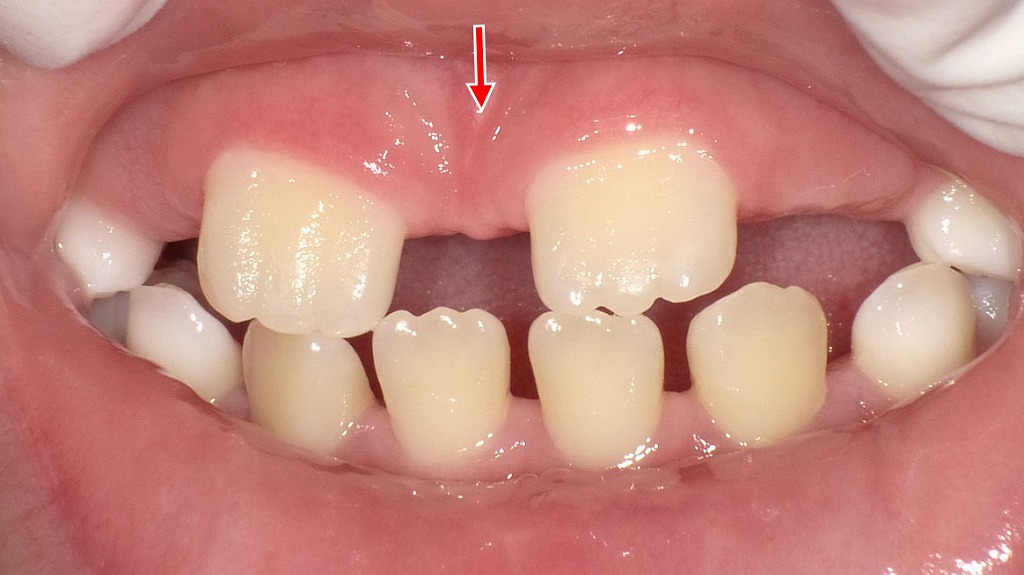

この画像は、上顎前歯(中切歯:いわゆる「前歯の真ん中2本」)の間に正中離開(せいちゅうりかい)が見られる状態です。赤い矢印が指している部分が離開の位置です。

歯が小さい、あるいは歯列の幅が広い場合も、自然にすき間ができます。 - 永久歯の萌出途中

子どもの場合、永久歯が生え変わる途中で一時的に正中離開が見られることがあります。これは「見にくいアヒル時代」と呼ばれ、自然に閉じるケースも多いです。 - 咬合(かみ合わせ)の影響

上顎の前歯(中切歯)が生えそろう過程で、一時的に正中離開(前歯のすき間)がみられる状態です。永久歯の萌出途中ではよく見られる生理的な現象で、犬歯など周囲の歯が生えてくることで、自然にすき間が閉じていくケースも少なくありません。経過観察が基本となりますが、すき間が大きい場合や長期間改善しない場合は、歯科医院での評価が大切です。